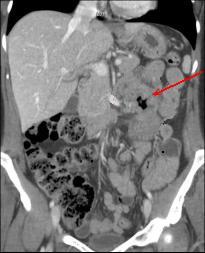

Mema cas ( fleche

rouge ) en coupe cornale ( frontal )

| Adenocarcinoma du duodenum a

extension locale vers le pancreas ( fleche rouge ) .

Dilatation du duodenum en amont |

Image TDM en coupe

coronale : Tumeur addeno carcinoma du jejunum

proximale a extension ganglionaire ( fleche rouge )

. Dilatation du jejunum en amont et aval . |